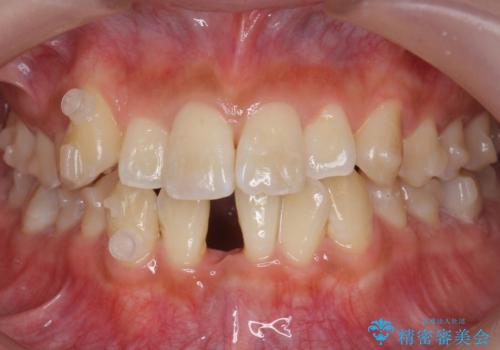

八重歯をインビザラインで 抜歯矯正

- 八重歯を主訴に来院。

出来るだけワイヤー矯正を避け、抜歯も最小限の本数をご希望でした。

下の前歯のみ1本抜歯しています。